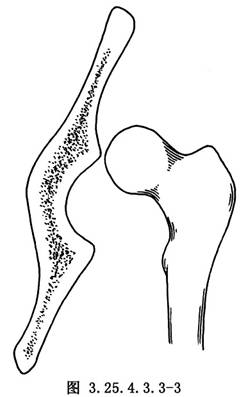

用4mm直徑斯氏針於大粗隆下緣向股骨頭中央鑽洞,將大粗隆基底帶蒂的髂脛束條縫成管狀,用有孔探針由大粗隆基底的骨洞穿入,由股骨頭中心拉出。再於髖臼中央偏前方,用骨鑽鑽洞,由髂骨內面的骨洞放入探針,將再造的圓韌帶由洞內拉出,將股骨頭復位,將圓韌帶拉緊與髖臼上緣的骨質和肌附麗再縫合固定,或於髂前下棘處鑽洞成襻狀縫合固定(圖3.25.4.3.3-3~3.25.4.3.3-6)。